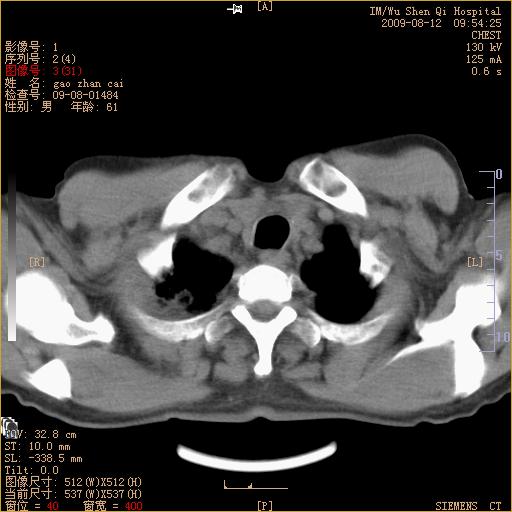

标题: CT21567:咳嗽,咳痰,发热半月余 [打印本页]

标题: CT21567:咳嗽,咳痰,发热半月余